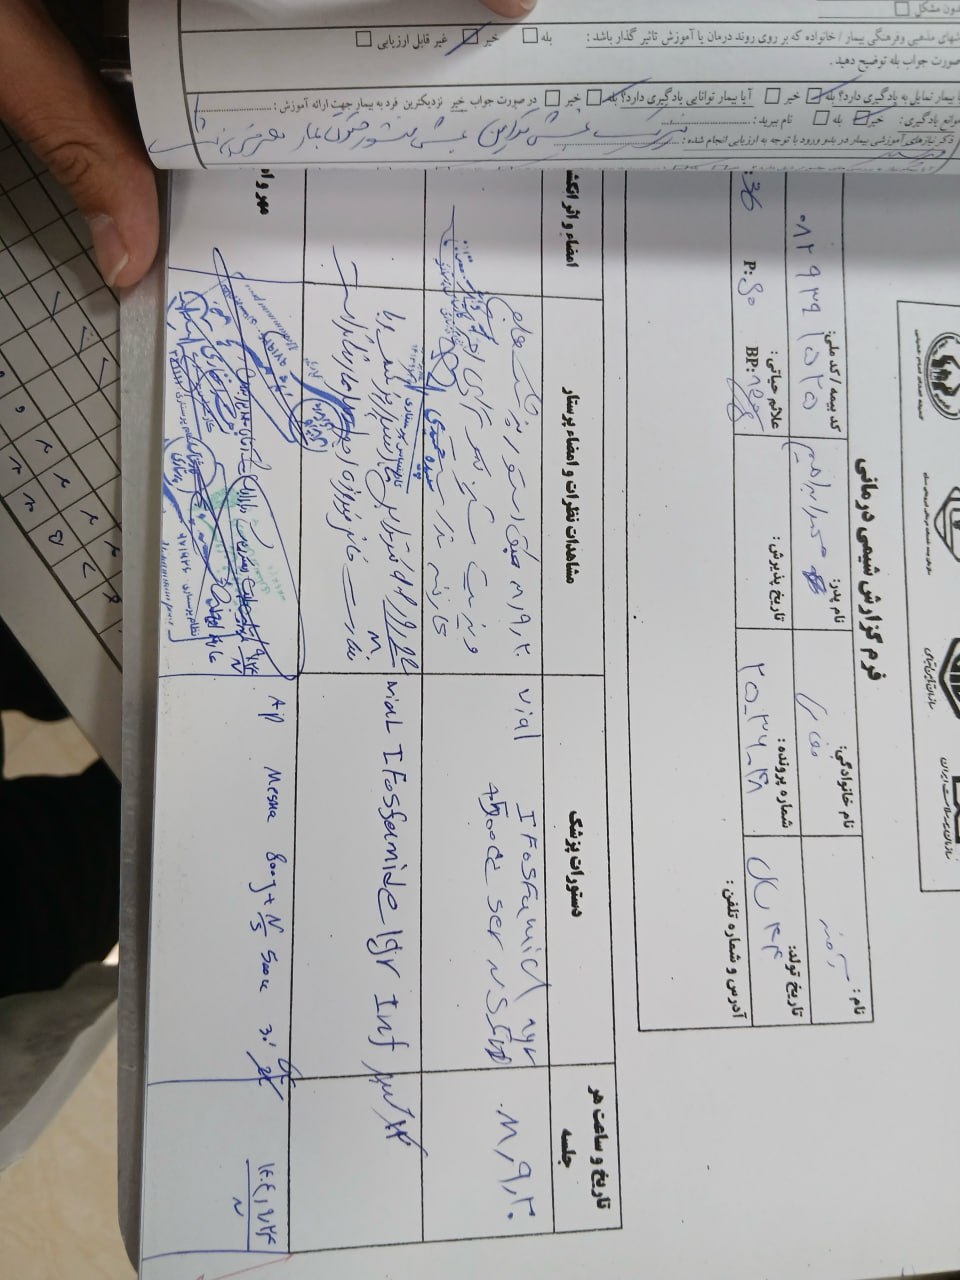

(تصویر مربوط به این مراجعه نیست) Other:

(تصویر مربوط به این مراجعه نیست) Other:

(تصویر مربوط به این مراجعه نیست) Other:

(تصویر مربوط به این مراجعه نیست) Other:

به ترتیب؛ روز ها: ۱۹ آبان, ۲۸ آذر, ۲۹ آذر, ۳۰ آذر

به ترتیب؛ روز ها: ۱۹ آبان, ۲۸ آذر, ۲۹ آذر, ۳۰ آذر

۱۹ آذر

۱۹ آذر

به ترتیب؛ روز ها: ۲۸ آذر, ۲۹ آذر, ۳۰ آذر, ۱ دی

۱ دی